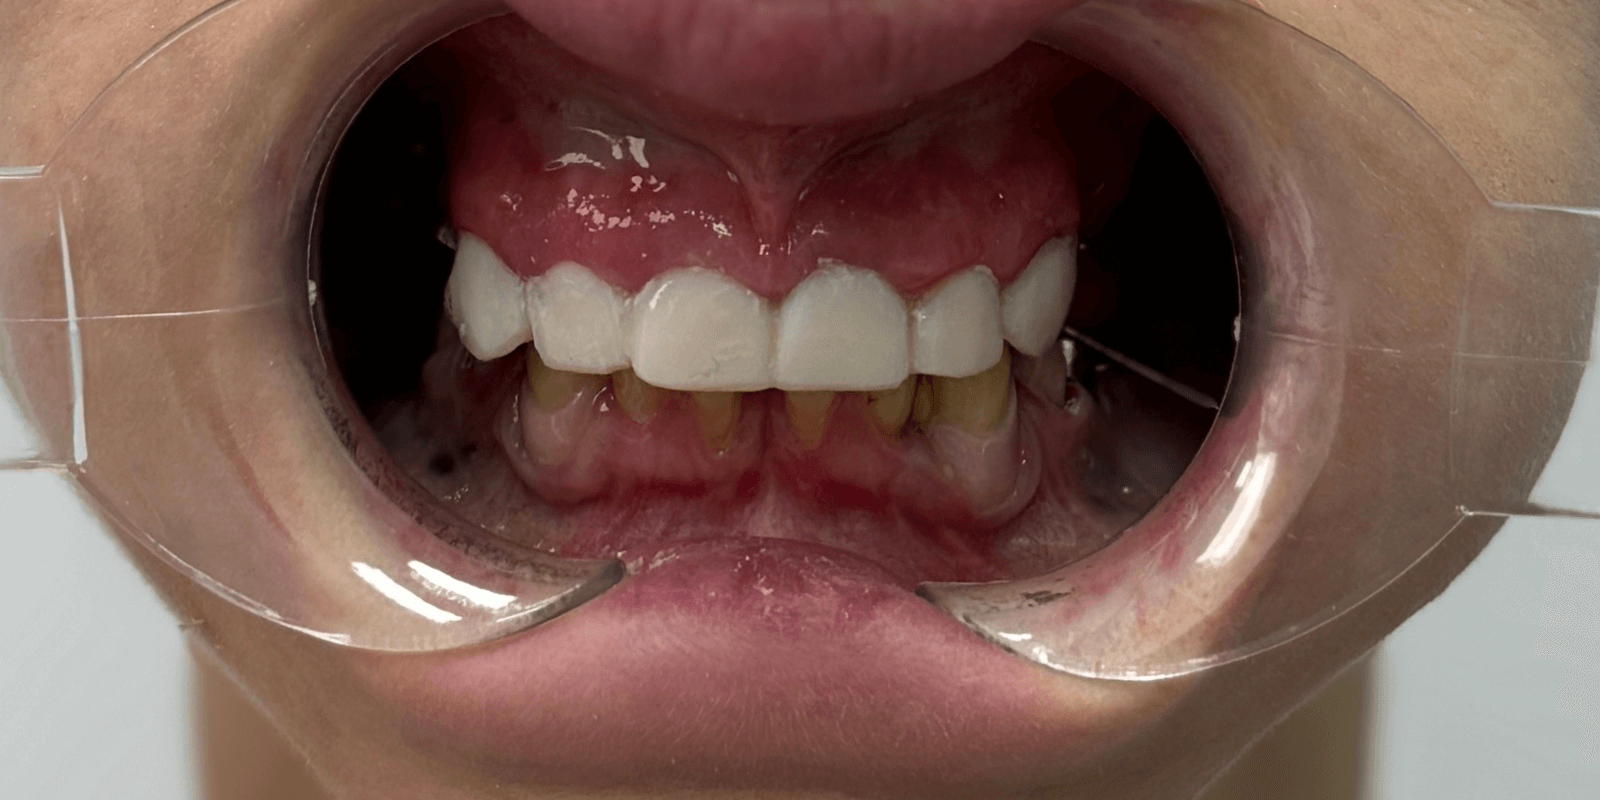

Итог

Мы не просто вылечили зубы. Мы собрали улыбку по частицам, как мозаику — с терпением, заботой и профессионализмом. Женщина, когда-то боявшаяся открыто говорить, теперь смеется с уверенностью. Она вернулась не только к врачу – она вернулась к себе.